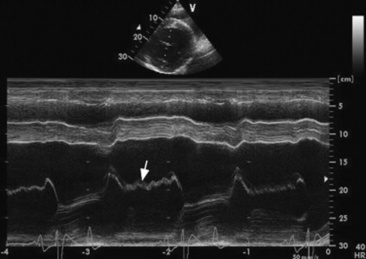

Clinical Pathology

Diagnosis of valvular disease is best performed with a complete echocardiographic examination including M-mode, two-dimensional, and Doppler echocardiography. Two-dimensional echocardiography is superior to M-mode for detection of valvular abnormalities (Figs. 30-8 and 30-9), measurement of valvular masses (Fig. 30-9, B), and the global assessment of ventricular function, but chamber enlargement, high-frequency vibrations of the valve leaflets, and shortening fraction (an indication of ventricular systolic function) can be determined by both. Pulsed wave, continuous wave, and color flow Doppler echocardiography can be used to semiquantitate the severity of valvular regurgitation.92-97 The size of the regurgitant jet detected with pulsed wave or color flow echocardiography is one indicator of the severity of the valvular insufficiency.98 The duration of the mitral regurgitation jet is also important in assessing severity. Clinically insignificant jets of regurgitation are detected only just behind the valve when it is closed. Valvular insufficiency is mild when the jet occupies one third or less of the receiving chamber, moderate when the jet occupies greater than one third but less than two thirds of the receiving chamber, and severe when the jet occupies greater than two thirds of the receiving chamber.

image

Fig. 30-8 Two-dimensional echocardiographic image obtained from the left parasternal window of a ruptured mitral chorda tendineae (arrow) in the left atrium of a gelding with mitral regurgitation and a honking pansystolic murmur.

image image

Fig. 30-9 Echocardiograms of a bacterial endocarditis lesion on the aortic valve of a horse. The lesion can be seen on the aortic valve M-mode (A) as a thick echoic band (arrow) and is measured in the two-dimensional echocardiographic image of the left parasternal long axis view (B).